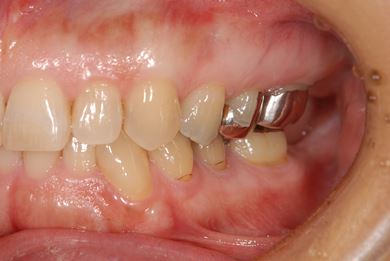

主訴 噛むと痛い。(咬合痛がある)

治療前

• 治療前